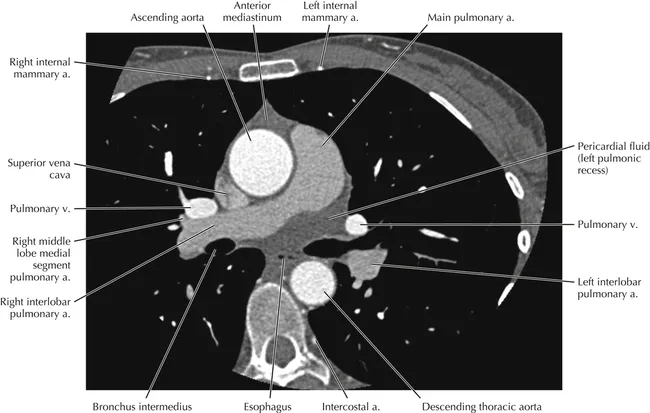

- CT (Axial):

- Ascending aorta is anterior to the descending aorta.

- Pulmonary artery is anterior and to the left of the aorta.